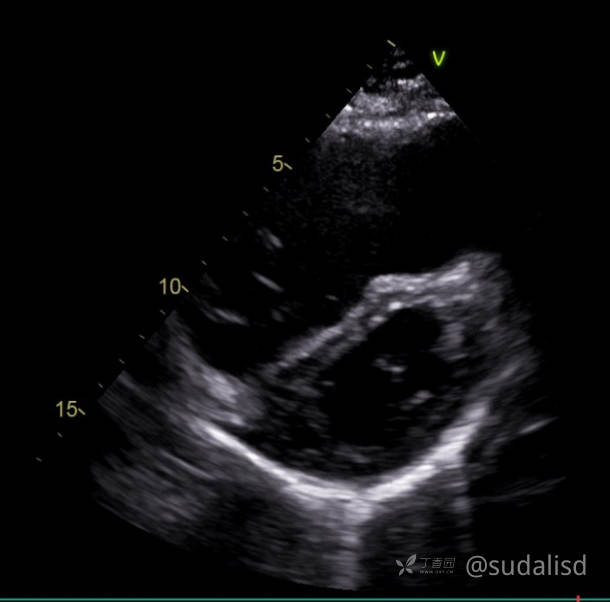

心脏彩超心尖短轴切面如下图。